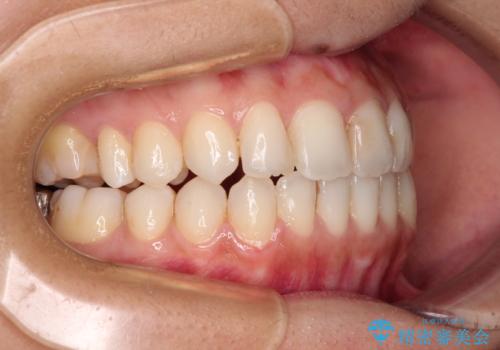

オープンバイトによる見た目を治したい インビザラインでの矯正治療

- オープンバイトのため、話しているときの見た目が気になるとのことで来院された患者様です。

下顎骨は左側にシフトしており、咬み合ったときには奥歯と前歯の一部しか接触していない状態でした。

骨格的な左右差は歯列矯正は改善できないため、上下歯列が全体的に接触することをゴールとしてインビザラインにて矯正治療を行うこととしました。

前歯のデコボコの解消と並行して上下の奥歯を圧下させるようにすることで、前歯を接触させるように計画しました。

上下の隙間に舌が入り込むことがオープンバイトの原因であったため、舌の筋肉のトレーニングも並行して行い、後戻りの抑制を図りました。